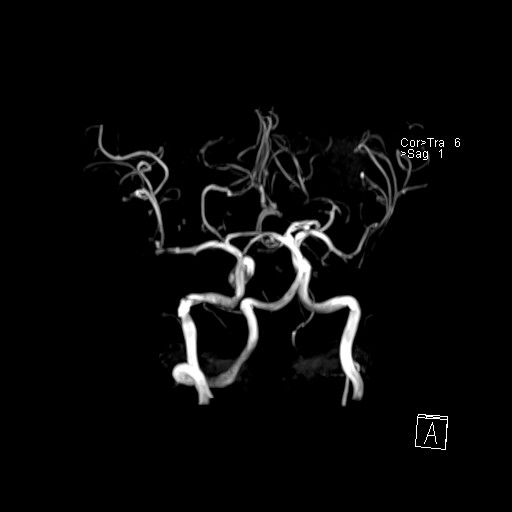

239716 - VILLANUEVA, WILLIAM A. - Number 2 |

|

239716 - VILLANUEVA, WILLIAM A. - Number 2 |